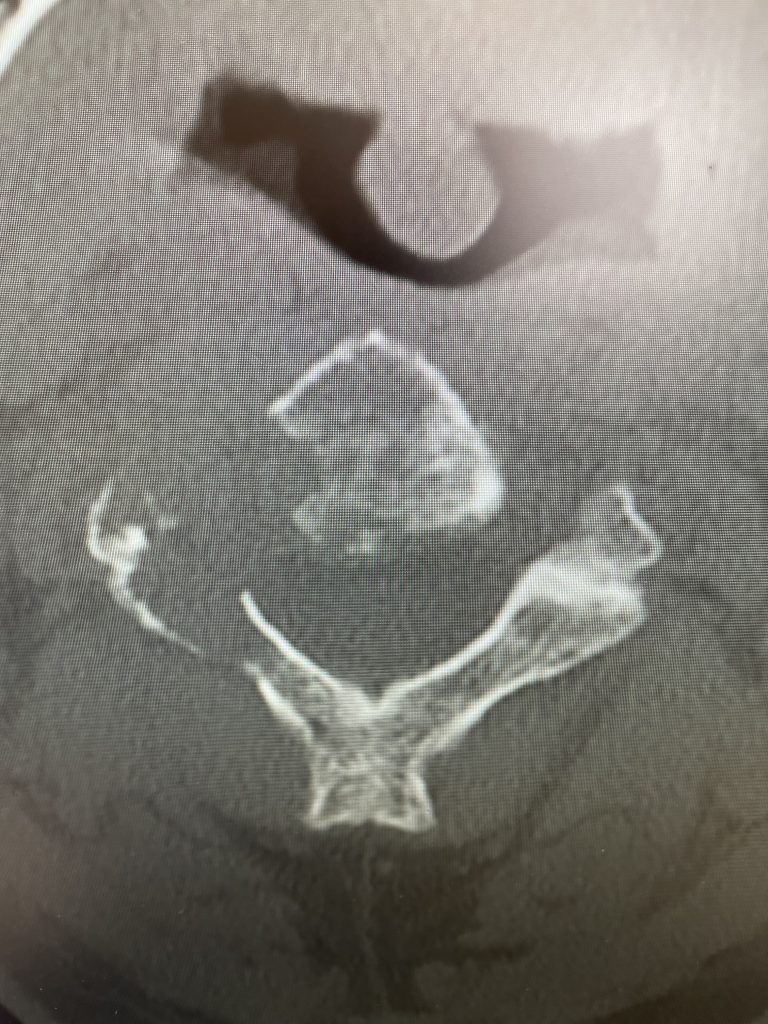

Fig 1: Sagittal and axial CT scan showing a lyric C2 lesion with extension into the posterior elements on the right side

Here is a tough case: This is a 72 year-old male who presented with several months of progressive neck pain without symptoms of the arms or legs. He had a history of prostate cancer for which he was treated. He had a biopsy of a hip lesion which was consistent with Paget’s disease, a benign but aggressive disease of the bone. He had imaging studies that were consistent with a destructive lytic C2 bony vertebral body lesion with extension into the posterior bony ring and possibly affecting C3 vertebral body (Fig 1). The patient’s urologist didn’t believe the patient had metastatic prostate cancer since his PSA was not elevated. The lesion itself was also not consistent with metastatic prostate cancer as they are usually blastic or bone forming lesions not bone destroying. His oncologist had initially sent us the patient with the thought that this was Pagets’s disease. Paget’s disease rarely affects the cervical spine and the bony appearance is more heterogeneous with a “picture-frame” appearance and hyperdense and not lytic. The patient underwent a PET scan which was “hot” consistent with malignant tumor. The patient underwent a bone marrow biopsy and had blood work consistent with a multiple myeloma diagnosis. The patient underwent radiation treatment with 25 fractionated cycles. The patient was given one percocet to control his pain by his oncologist.